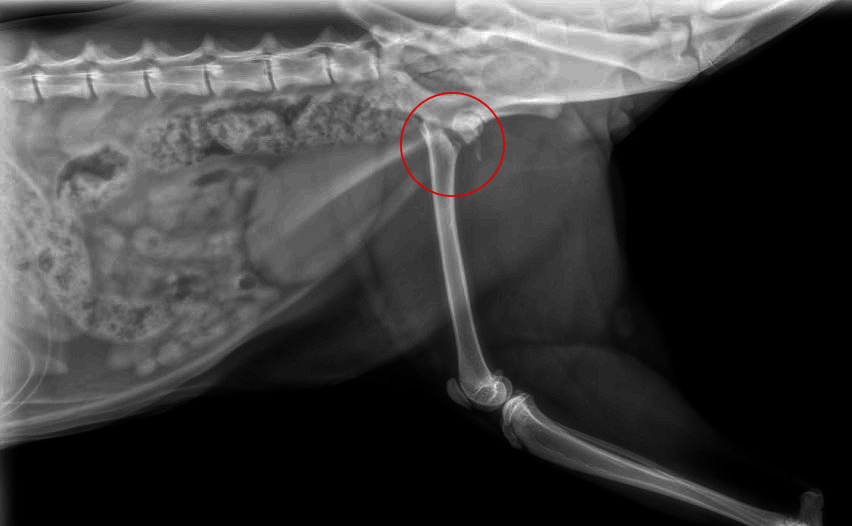

We're Miranda and Steven, and we’re reaching out for support during one of the most difficult times we’ve faced as pet parents. Our beloved cat Grimm was recently hit by a car and has broken his femur. We rushed him to the emergency vet, and the news we received shattered us: Grimm will need major surgery or a possible amputation in order to live a normal life without pain again.

The costs associated with his treatment are already nearing $6,000—this includes emergency visits, X-rays, medication, transportation, recovery supplies, and the time we’ve taken off work to care for him day and night. While we’re doing everything we can to cover part of these expenses, we simply can’t do it alone.